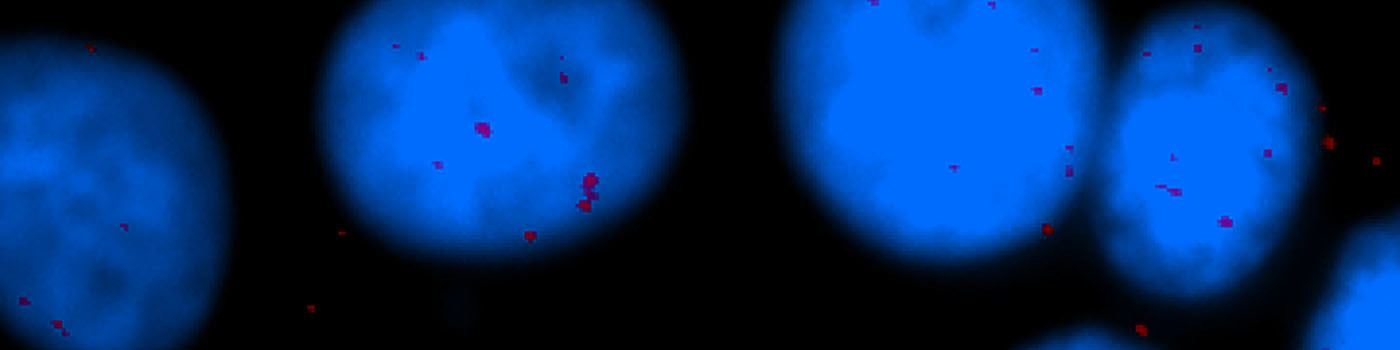

One field of view of the original cell line image (scaled down to fit this space).

The number of in situ PLA signals per nuclei was counted by automated image analysis. Fully automated nuclei delineation was initiated by identifying cell nuclei using the signal from the nuclear Hoechst staining (blue). Touching nuclei were separated using a combination of distance transformation and watershed segmentation. In situ PLA signals were counted by enhancing point-like signals and defining a true signal as a local intensity maximum above a background threshold.

PLA plus and minus probes (containing the secondary antibodies conjugated with oligonucleotides) were added and incubated at 37°C for 2 h. Further oligonucleotides were added, to allow hybridization with PLA probes and ligase. The DNA was then amplified and detection carried out using the 563 detection kit (including Hoechst 33342 dye nuclear staining), resulting in red fluorescence signals. Finally, the slides are mounted with Vectashield mounting media (Vector Lab., Inc., Burlingame, CA, USA).